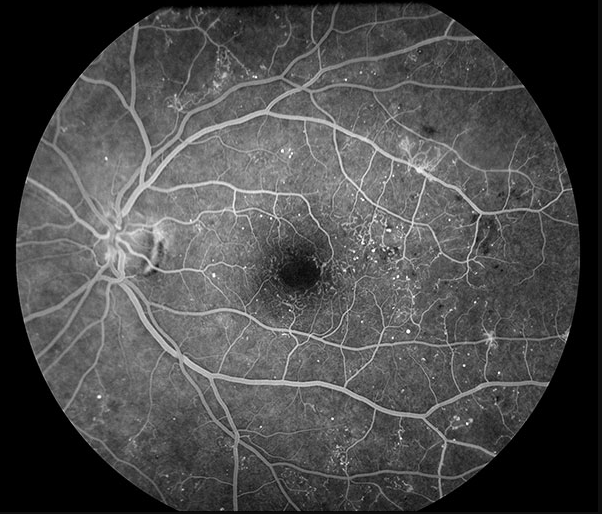

진단: 안저검사 또는 FAG에서 **신생혈관(neovascularization)**이 확인되면 PDR로 진단합니다. 망막 허혈에 의한 VEGF 상승이 원인이며, NPDR 단계에서는 보이지 않던 비정상적 새 혈관이 망막 표면/시신경유두/홍채에 발생하는 것이 핵심 소견입니다.

DME (당뇨황반부종)

진단: OCT에서 황반부 망막 두께 증가(중심와 두께, CST 증가) 또는 안저검사에서 황반부 부종/경성삼출물이 확인될 때 진단합니다. NPDR/PDR 어느 단계에서든 동반 가능하며, 당뇨망막병증에서 시력저하의 가장 흔한 원인입니다.

- Center-involving DME (CI-DME): 중심와(fovea) 침범 — 시력에 직접 영향, anti-VEGF 치료 대상

- OCT: DME 평가의 gold standard. CST, 망막내/하액 평가

- FAG (Fluorescein Angiography): 비관류 영역, 미세동맥류 누출, 신생혈관 확인